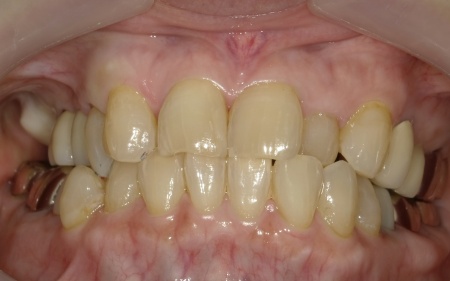

治療前

治療後